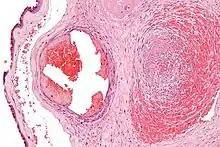

Micrograph showing fibrin (dark pink amorphous material) in a blocked vein surrounded by extravasated red blood cells (right of image). An artery (left of image) and the amnion (far left of image) is also seen. Placenta in a case of fetal thrombotic vasculopathy. H&E stain.